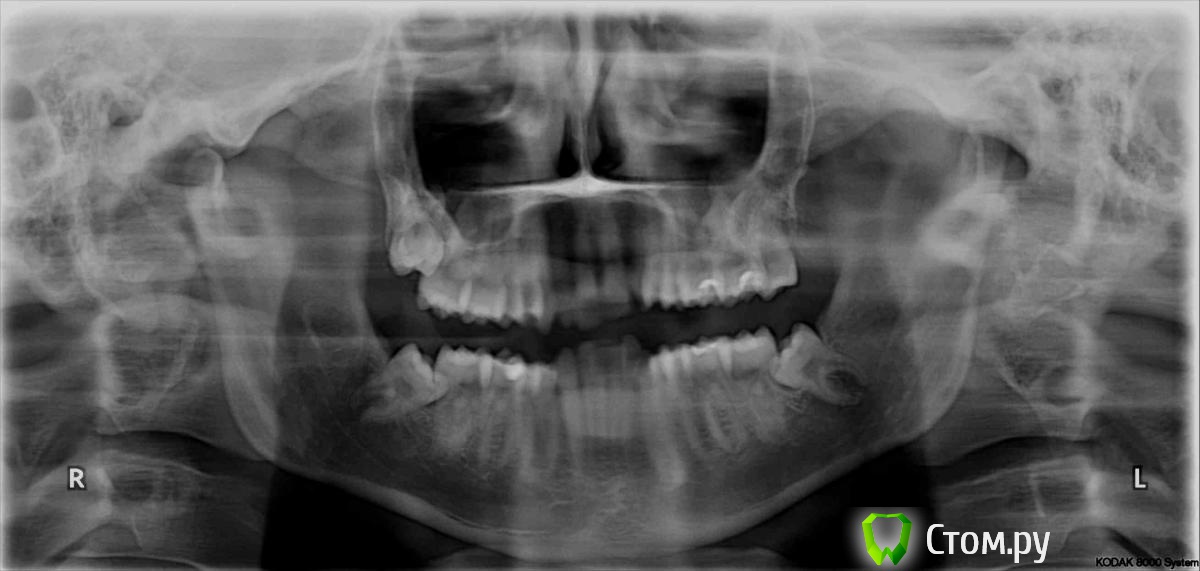

Татьяна_200 Опубликовано 17 августа, 2014 Поделиться Опубликовано 17 августа, 2014 Здравствуйте, планирую установить брекеты . Консультировались у ортодонтов, кто-то рекомендует удалить восьмерки перед лечением.Один врач сказал, что можно их удалить в любой момент, а сейчас будет ставить без удаления. Очень срочно нужен совет , нужно ли удалить их перед лечением или можно будет в любое время, даже после снятия брекетов? Ссылка на комментарий

samsonov Опубликовано 17 августа, 2014 Поделиться Опубликовано 17 августа, 2014 Нижние, имхо, актуальнее удалить раньше, их локализация создаёт предпосылки скученности и воспаления, однако в правильных руках можно все три сразу убрать и заморачиваться.) 1 Ссылка на комментарий

Татьяна_200 Опубликовано 20 августа, 2014 Автор Поделиться Опубликовано 20 августа, 2014 Спасибо за ответы. Понятно, что удалять нижние нужно в любом случае, но можно ли оставить верхние восьмерки? Влияют ли они на ближайшие зубы? Ссылка на комментарий